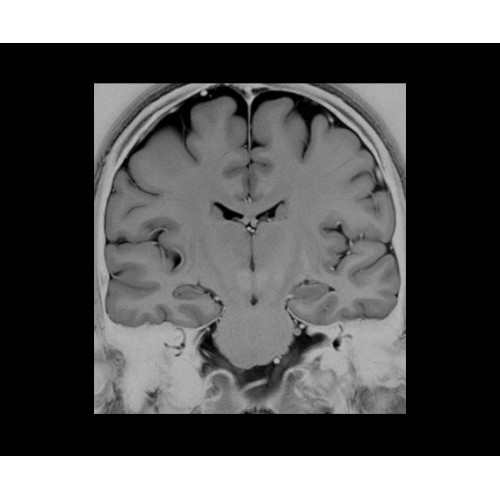

SIGNA PET/MR 3.0T — это гибридная система, в которой совмещаются две принципиально разные технологии — магнитно-резонансную томографию (МРТ) и позитронно-эмиссионную томографию (ПЭТ). Система отличающийся высокой чувствительностью и эффективностью и предназначена для диагностики в области онкологии, неврологии, кардио-васкулярных исследований, исследований воспалительных процессов.

Компания GE Healthcare представляет революционную, полностью интегрированную систему SIGNA PET/MR1, в которой сочетаются времяпролетная технология (TOF) и возможности напряженности магнитного поля 3.0 Тл. Мы поможем вам поднять исследования на более высокий уровень. SIGNA PET/MR позволяет достичь впечатляющей точности и скорости исследований, а благодаря новейшей технологии реконструкции Q.Clear2 качество изображений улучшается в два раза. Кроме того, в систему включен полный набор клинических приложений и гибких катушек для проведения любых видов исследования, открывая для вас возможности визуализации, о которых вы даже не догадывались.

Кроме того, в результате использования технологии TOF и инновационной технологии реконструкции Q.Clear вы сможете добиться прекрасного соотношения сигнал/шум. А благодаря технологии нулевого времени эхо (ZTE) визуализировать костную структуру без ионизирующего излучения. Все эти разработки для улучшения качества сканирования и точности анализа помогут вам использовать весь потенциал ПЭТ/МРТ.

Впечатляющие клинические возможности

Система SIGNA PET/MR предлагает впечатляющие клинические возможности и открывает доступ к наиболее полным пакетам программных приложений.

• Специальный пакет приложений для измерения и сравнения объемных изображений ЦНС с нормами поможет вам в диагностике нейродегенеративных заболеваний, а дополнительные инструменты визуализации — в постановке точного диагноза с помощью бета-амилоидов и радиоизотопных маркеров ФДГ.